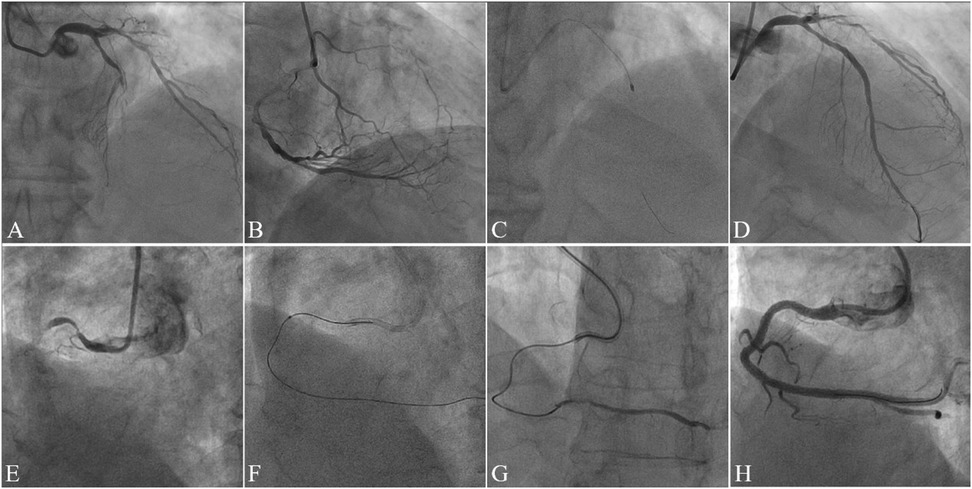

This study analyzed medical records of consecutive patients who underwent ELCA or RA at Guangdong Provincial People's Hospital (July 2020–August 2023). The choice between ELCA and RA was made at the operator's discretion, based on a comprehensive assessment of specific lesion characteristics. From 525 initially screened procedures, we identified 89 patients with CTO exhibiting device-uncrossable or balloon-undilatable lesions. Ultimately, 75 eligible patients were included in this study. The inclusion and exclusion process of the study subjects was detailed in Figure 1. The inclusion criteria for this study strictly adhered to the following points: (1) age ≥18 years; (2) CTO-PCI indications including angina symptoms and/or objective evidence of reversible myocardial ischemia (perfusion imaging/stress testing). The exclusion criteria were: (1) age >85years or high bleeding risk contraindicating surgery; (2) contraindications to dual antiplatelet therapy; (3) history of radiation skin injury; (4) severe renal impairment without dialysis commitment. This study has been strictly approved by the Ethics Committee of Guangdong Provincial People's Hospital (approval number: KY2023-716-01), and in accordance with regulations, participants are not required to sign an informed consent form. Figure 2 presents representative cases of CTO-PCI, one performed with ELCA and the other with RA.

Figure 2

Angiographic series of eight grayscale images labeled from A to H. Each panel shows different views of coronary arteries with varying levels of contrast-enhanced visualization, highlighting the arterial structures and possible blockages or abnormalities.

Figure 2. Case illustrations of CTO-PCI with rotational atherectomy (RA) and excimer laser coronary atherectomy (ELCA). Case 1. (A) Preprocedural angiography demonstrating mid-to-distal left anterior descending artery (LAD) occlusion (TIMI 0 flow); (B) Right coronary artery (RCA) angiography showing collateral circulation supplying the distal LAD; (C) Rotational atherectomy (RA) performed after failed antegrade wiring and balloon uncrossability; (D) Final angiography post-stenting demonstrating restored patency (TIMI 3 flow). Case 2. (E) Preprocedural angiography revealing proximal RCA occlusion (TIMI 0 flow); (F) Excimer laser coronary atherectomy (ELCA) initiated after failed antegrade microcatheter advancement; (G) Post-ELCA microcatheter advancement to the distal RCA true lumen (confirmed by contrast injection); (H) Final angiography post-stenting showing optimal vessel reconstruction.